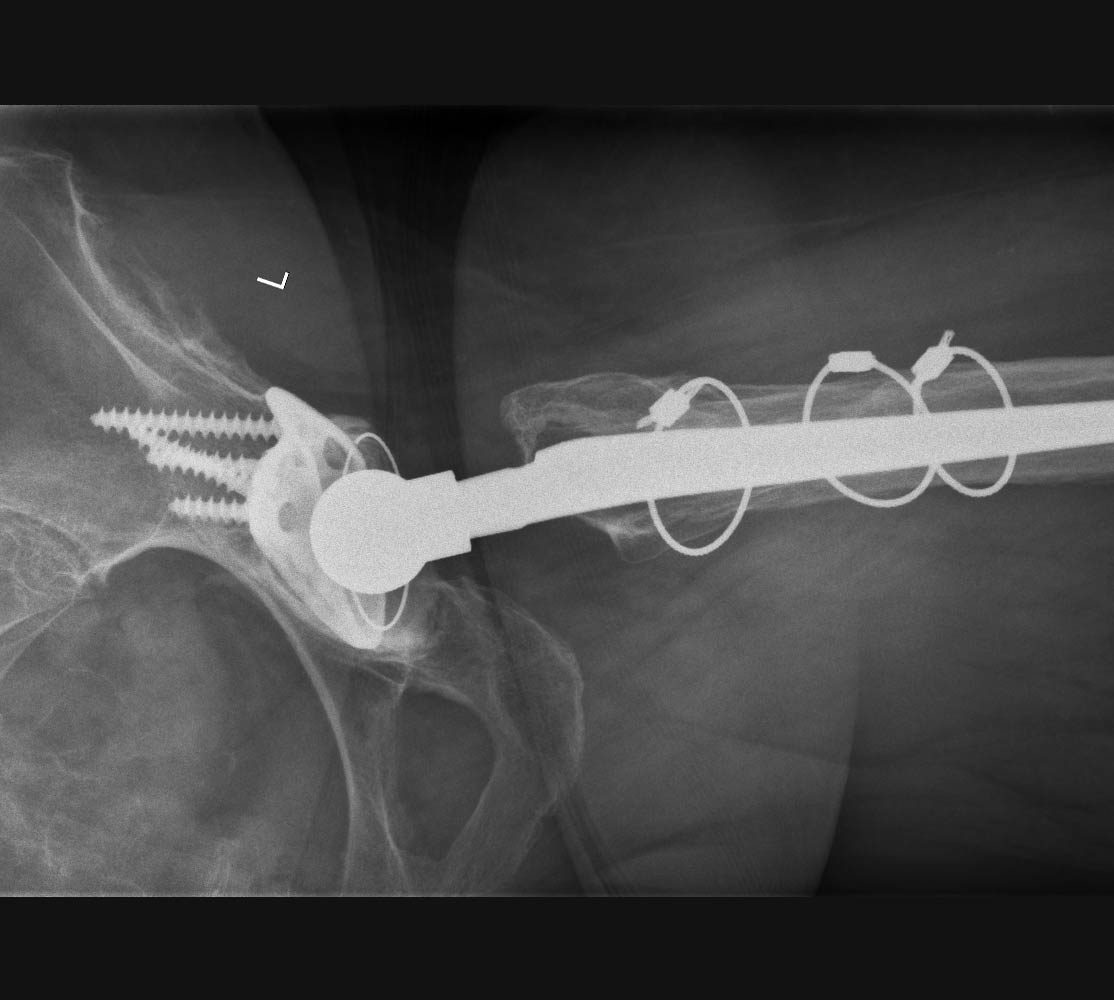

Inverse Schulterprothese (auch Deltaprothese)

Bei ausgedehnten, nicht mehr rekonstruierbaren Rotatorenmanschetten-Defekten spricht man von einer Defektarthropathie. Die betroffenen Patienten leiden unter starken Bewegungseinschränkungen der Schulter. Der Arm kann nicht mehr oder nur unter starken Schmerzen angehoben werden. Der Oberarmkopf wandert nach oben unter das Schulterdach und verhindert dann eine normale Funktion.

Zunächst versuchen wir auch in diesem Fall, mit konservativen Maßnahmen wie Physiotherapie die Funktion der Schulter und die Beschwerden zu verbessern. Bringt dies nicht den gewünschten Erfolg, kann in diesen Fällen durch die so genannte inverse Schulterprothese – oder auch „Deltaprothese“ – die Funktion der Schulter wiederhergestellt werden.

Bei der inversen (umgekehrten) Schulterprothese werden die Gelenkpartner des Schultergelenks vertauscht: An der Stelle, an der beim Menschen der Oberarmkopf liegt, wird eine Gelenkpfanne eingebracht und dort, wo sich bei normaler Anatomie die Gelenkpfanne befindet, wird eine dem Oberarmkopf ähnliche Halbkugel befestigt. Die inverse Prothese eignet sich deswegen für Patienten mit zerstörter Rotatorenmanschette, weil sie das Drehzentrum der Schulter nach unten und innen verlagert. So ist man für die Funktion der Prothese nur auf einen Muskel angewiesen – und zwar auf den Deltamuskel. Die Schulter kann dann anschließend wieder normal und schmerzfrei bewegt werden.

Röntgenbild Inverse (Delta-)Schulterprothese

Links: Abbildung einer Defektarthropathie, der Oberarmkopf wandert nach oben unter das Schulterdach.

Rechts: Durch die Umkehrung des Kopf-/Pfannenprinzips kann der Oberarmkopf unten gehalten werden, so dass andere Muskeln (Delta-Muskel) die Funktion übernehmen können.

Schematische Darstellung der Implantate

Nach Implantation